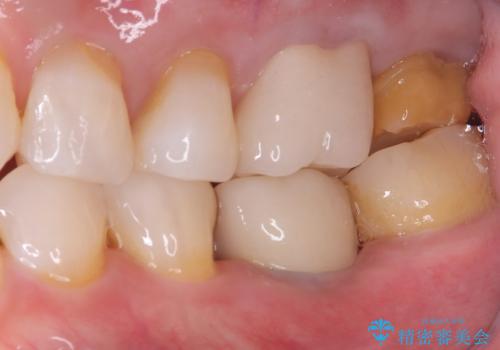

【セラミッククラウン】詰め物と歯の境目に汚れが溜まる

- 主訴:詰め物と歯の奥が側の境目に物がいつも溜まってしまう

保険適応のメタルインレーと歯質との間に不適合な箇所を認め、補綴物のやり替えでの治療となりました。インレーからクラウンへ補綴物の形態を変更し、素材は清掃性・適合性・審美性の点からセラミッククラウンでのやり替となりました。